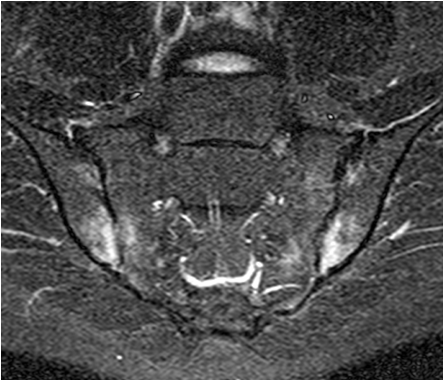

Inflammatory synovial changes and subchondral edema are well seen on MRI. MRI is more sensitive and is being used with increased frequency to detect and stage inflammatory nvolvement of the sacroiliac joint in patients with ankylosing spondylitis.

Fig. 16. T1 weighted and STIR images of the sacroiliac joints in a young patient with low back pain. Low signal areas on T1 correspond with edema seen on STIR. Note the joint space narrowing and the more pronounced subchondral changes in the iliac bone as compared to the sacrum.